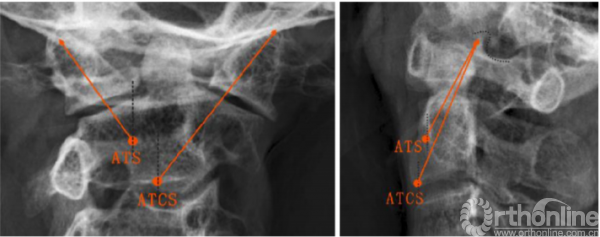

ATS和ATCS固定的轨迹可通过正、侧位X线片上的解剖标志来确定。在正位X线片中,螺钉轨迹朝向C1上关节突上外侧角,与侧块外侧缘间隙为2-3mm(图3,左)。然后测量α角,即ATS与ATSC螺钉相对于矢状面所形成的理想外展角。在侧位X线片中,ATS和ATCS固定方向均朝向C1上关节突后上角,并与上关节突后缘的间隙为2.3mm(图3,右)。此外,还测量了角β,即ATS与ATSC螺钉相对于冠状面所形成的理想倾斜角。将螺钉置入新鲜尸体标本后,在正、侧位X线片上分别测量ATS和ATCS的实际角α、β,以及ATCS和ATS的实际进钉点与C2椎体中线的横向距离。

图3正位和侧位x线片上ATS和ATCS的螺钉轨迹,(左)所有螺钉对准C1上关节突上外侧角;(右)所有螺钉对准C1上关节突上角(点附近);ATCS,前路经关节交叉螺钉;ATS,前路关节交叉螺钉

The ATS and ATCS trajectories were determined using the landmarks visible on anteroposterior and lateral x-rays. On the anteroposterior view, screw trajectories were aimed at the superolateral corner of C1 superior articular process, leaving 2–3 mm clearance from lateral margin of the lateral mass (Fig. 3, left). Then, the angle α, the ideal lateral angle of ATS and ATCS placement relative to the sagittal plane were measured. On the lateral view, the trajectories of ATS and ATCS were aimed at a point on the line between the superoposterior corner of C1 superior articular process and the superior end of the anterior arch, with 2–3 mm clearance from posterior margin of the superior articular process (Fig. 3, right). Moreover, the angle b, the ideal incline angle of the two screws placement relative to coronal plane were measured. After the screws were inserted into fresh cadaveric specimens, the actual angle a and b of ATS and ATCS were also measured on anteroposterior and lateral X-ray images, respectively, as well as the actual entry points of ATCS and ATS lateral from the midline of the C2 vertebrae.

Fig. 3 Trajectories of ATS and ATCS are shown on anteroposterior (left) and lateral radiographs (right). (left) All screws are aimed at the superolateral corner of C1 superior articular process (right) All screws are aimed at the superoposterior corner of C1 superior articular process (around dot). ATCS anterior transarticular crossing screw, ATS anterior transarticular screw